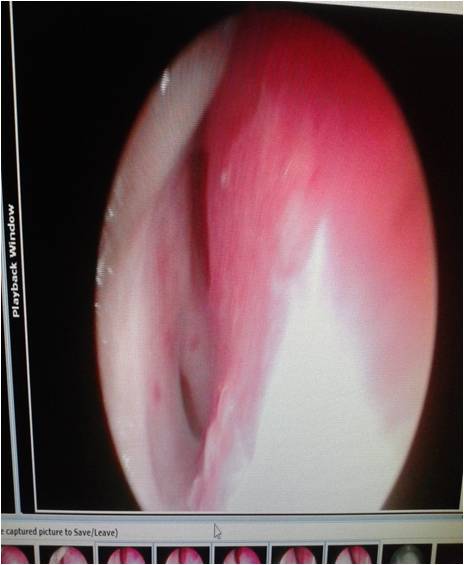

Osler Weber Rendu Syndrome (OWRS), or Hereditary Hemorrhagic telangiectasia (HHT) is an autosomal dominant disease presents with epistaxis, telangiactesia and multiorgan vascular dysplasia. Recurrent epistaxis is common in these patients and various local forms of therapy is tried to treat the condition, but there is lack of definitive and effective treatment. We present a patient of HHT with severe recurrent epistaxis successfully treated with thalidomide.